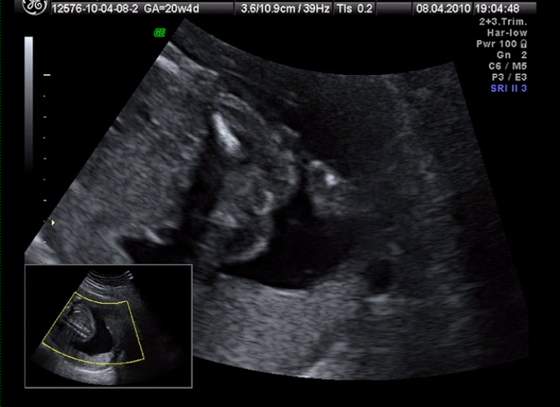

śliczna panienka rośnie :-)Przyszła kolej na moją śliczną córunię - mam nadzieję, że już jej nic nie wyrośnie, bo się przyzwyczaiłam... :-)

kolejno: uśmiech, pipulka, twarzyczka i krągła dupcia